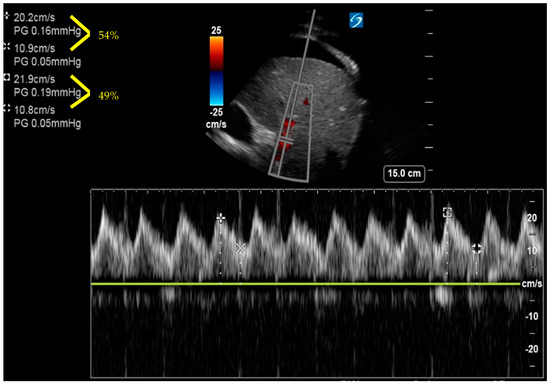

6. Venous Excess Ultrasound Score

- Beaubien-Souligny, W.; Rola, P.; Haycock, K.; Bouchard, J.; Lamarche, Y.; Spiegel, R.; Denault, A.Y. Quantifying systemic congestion with Point-Of-Care ultrasound: Development of the venous excess ultrasound grading system. Ultrasound J. 2020, 12, 16. [Google Scholar] [CrossRef]

- Longino, A.; Martin, K.; Leyba, K.; Siegel, G.; Gill, E.; Douglas, I.S.; Burke, J. Correlation between the VExUS score and right atrial pressure: A pilot prospective observational study. Crit. Care 2023, 27, 205. [Google Scholar] [CrossRef]

- Spiegel, R.; Teeter, W.; Sullivan, S.; Tupchong, K.; Mohammed, N.; Sutherland, M.; Leibner, E.; Rola, P.; Galvagno, S.M.; Jr Murthi, S.B. The use of venous Doppler to predict adverse kidney events in a general ICU cohort. Crit. Care 2020, 24, 615. [Google Scholar] [CrossRef]

- Andrei, S.; Bahr, P.A.; Nguyen, M.; Bouhemad, B.; Guinot, P.G. Prevalence of systemic venous congestion assessed by Venous Excess Ultrasound Grading System (VExUS) and association with acute kidney injury in a general ICU cohort: A prospective multicentric study. Crit. Care 2023, 27, 224. [Google Scholar] [CrossRef]

- Argaiz, E.R.; Rola, P.; Gamba, G. Dynamic Changes in Portal Vein Flow during Decongestion in Patients with Heart Failure and Cardio-Renal Syndrome: A POCUS Case Series. Cardiorenal Med. 2021, 11, 59–66. [Google Scholar] [CrossRef]

- Rola, P.; Miralles-Aguiar, F.; Argaiz, E.; Beaubien-Souligny, W.; Haycock, K.; Karimov, T.; Dinh, V.A.; Spiegel, R. Clinical applications of the venous excess ultrasound (VExUS) score: Conceptual review and case series. Ultrasound J. 2021, 13, 32. [Google Scholar] [CrossRef] [PubMed]